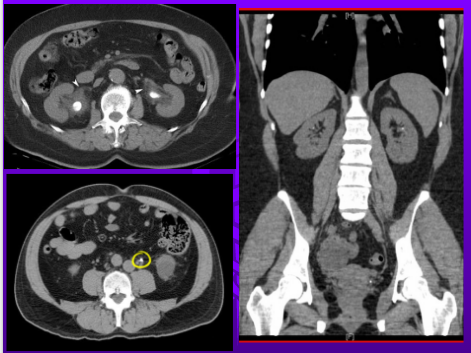

What is the gold standard to detect stones?

CT scan

Renal Stone CT Scan

CT SCAN IVP